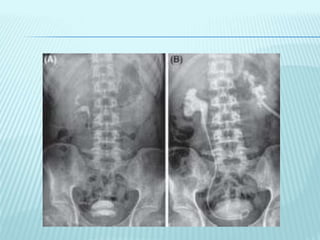

GROSS PHOTOGRAPH OF KIDNEY SHOWS MULTIPLE NECROTIC AREAS INVOLVING THE MEDULLA AND AT PLACES

DESTROYING RENAL CALYCES [FIGURE 1A]. CHRONIC TB PYELONEPHRITIS WITH DESTROYED RENAL CALYCES

[FIGURE 1B]. EPITHELIOID CELL GRANULOMAS WITH DENSE CHRONIC INFL AMMATORY INFI LTRATE IN RENAL

CORTEX. [FIGURES 1C, D, H AND E, X100]. FOCALMFORMATION OF LYMPHOID FOLLICLES [FIGURE 1E, H AND E, X40].

CROSS-SECTION OF URETER SHOWING ULCERATED UROTHELIUM BY A GRANULOMATOUS PROCESS [FIGURE 1F, H

AND E, X40]